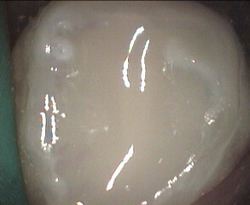

Unusual prevalent but superficial groove pattern on permenant molar after Sealed